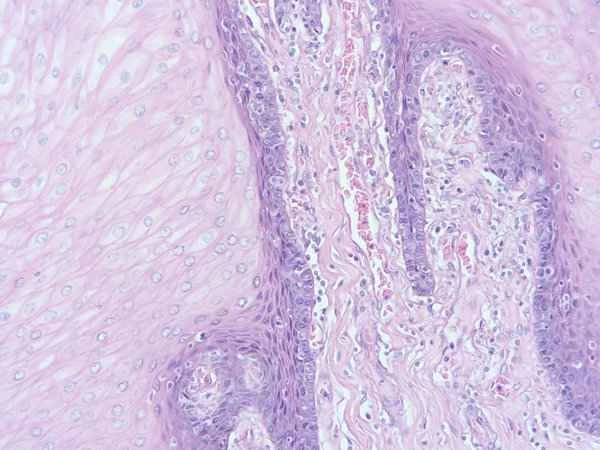

A raised, purplish lump on the inside of the lip can be caused by a variety of reasons. This could be due to a hemangioma, a submucosal cyst, or other types of oral mucosal lesions. A hemangioma is a benign tumor composed of blood vessels, while a submucosal cyst may be caused by fluid accumulation due to obstruction of the salivary gland duct.